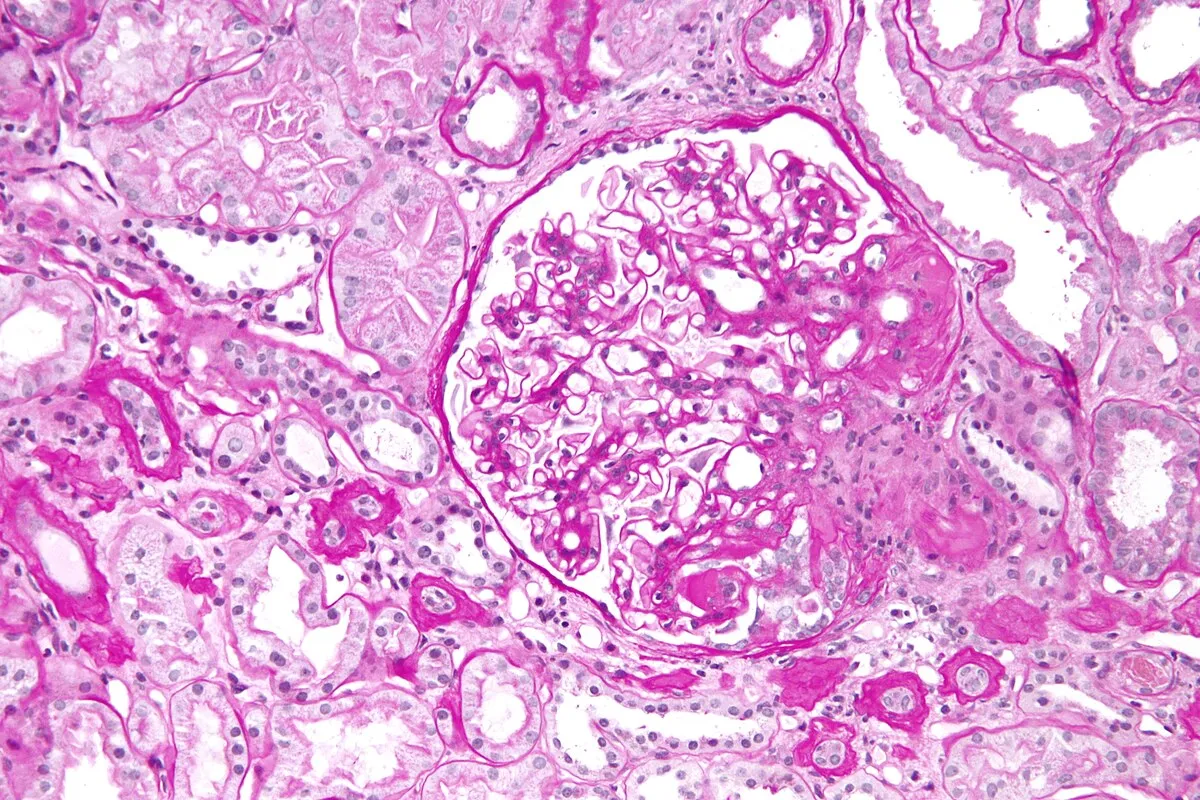

Injúria Renal Aguda (revisão Lancet 2025)